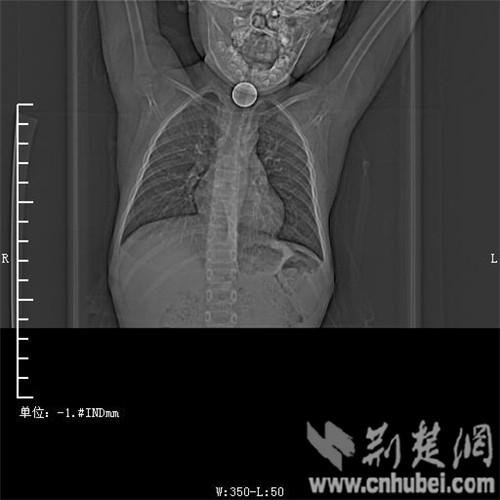

圖為:硬幣卡在了陽陽的喉部

消化內(nèi)主任方向明告訴記者,孩子送來時已經(jīng)是晚上8點(diǎn)15分,醫(yī)護(hù)人員立即給孩子拍胸部CT確定硬幣的位置,8點(diǎn)30分,方向明通過胃鏡下食管異物取出術(shù),成功的將這枚一元硬幣取了出來。1月5日上午,陽陽順利出院,醫(yī)生護(hù)士在他出院時不斷告訴他,以后千萬不要吞含異物。